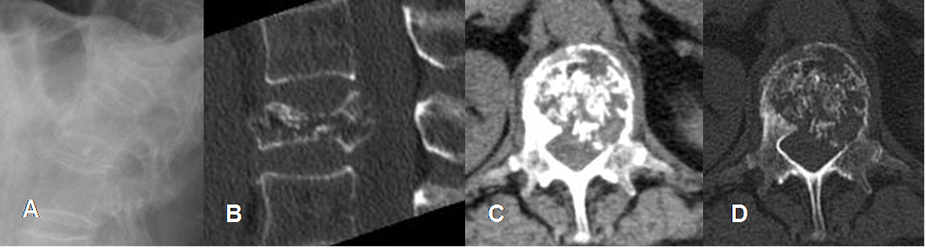

Fig 198. Mieloma.

A: Rx lateral, B: TAC reconstrucción sagital, C: TAC axial en ventana de tejido y D: TAC axial en ventana osea. Osteopenia generalizada, con fractura patológica en D11 y fragmento retropulsado.